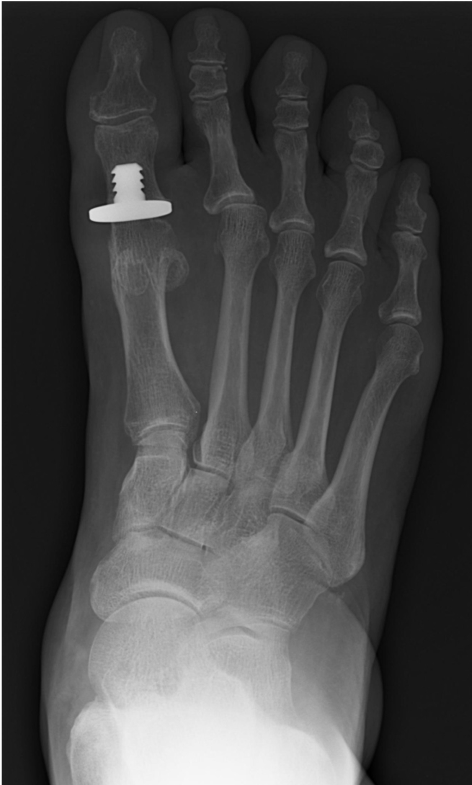

what is 1st MTPJ fusion?

Most reliable consistent treatment

Surface of the joint is debrided, fixation so bone crosses of the joint

what is 1st MTPJ hemiarthroplasty?